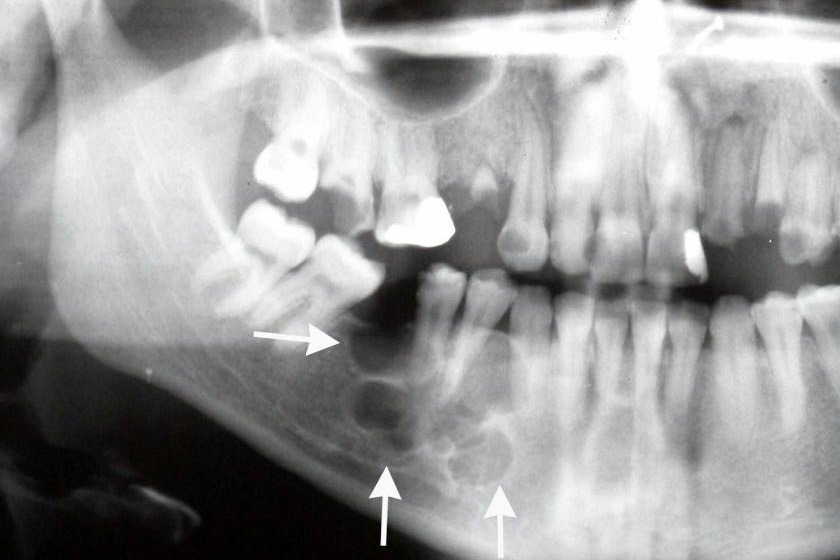

Ví dụ: Một bệnh nhân mất răng số 6, răng số 5 và số 7 bị nghiêng vào khoảng trống. Khi đó bác sĩ sẽ chỉnh nha trước để kéo răng 5 và 7 về đúng vị trí, tạo chỗ lý tưởng cho việc đặt Implant.

-  Bác sĩ cần chụp phim CT 3D để xác định vị trí trụ Implant có ảnh hưởng đến hướng dịch chuyển răng hay không.